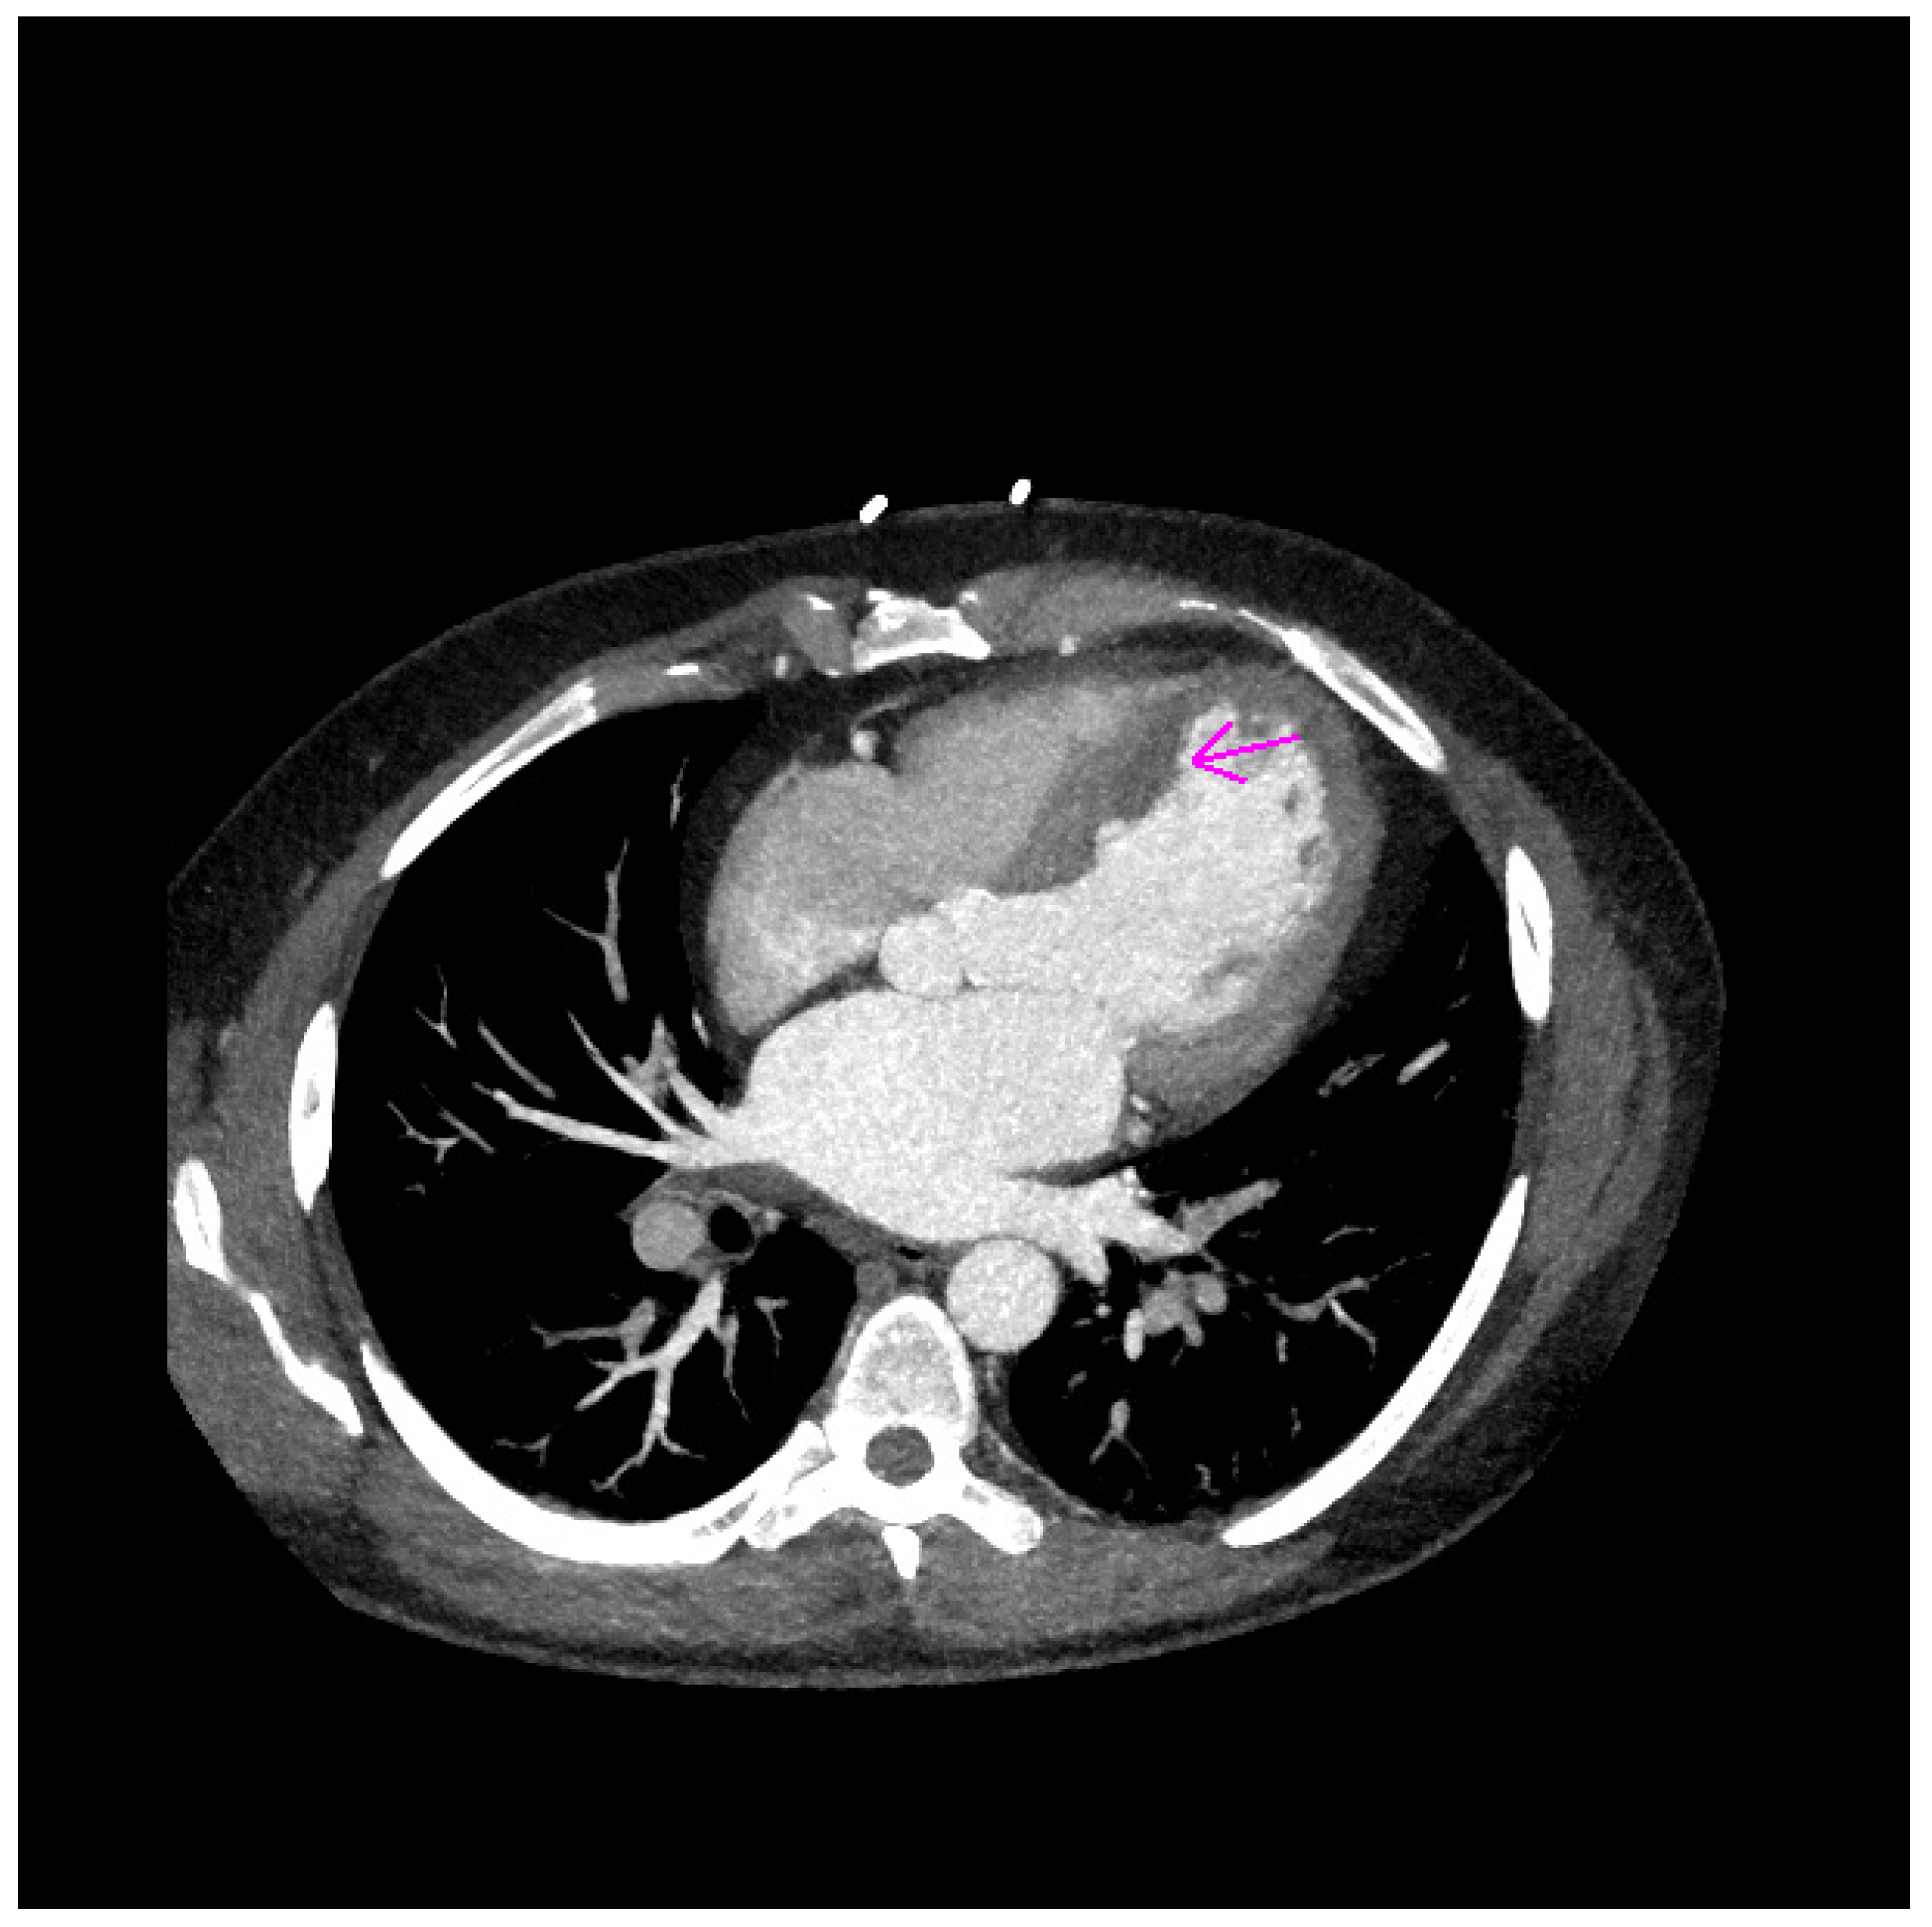

2. Case Report